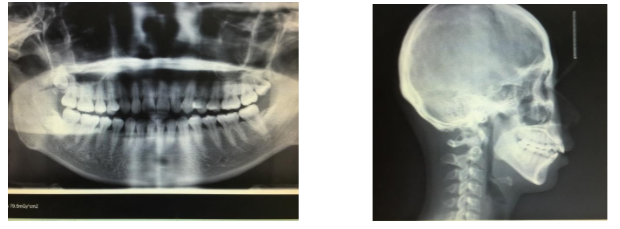

因为我已经拍过xray确认过我牙齿的健康情况了,所以就跳过了这一步,不过也可以附上之前在其他诊所拍的图,供大家欣赏。

大晚上看这种图可能不太好,但是也可以看出来我是明显的开咬合和过咬合。